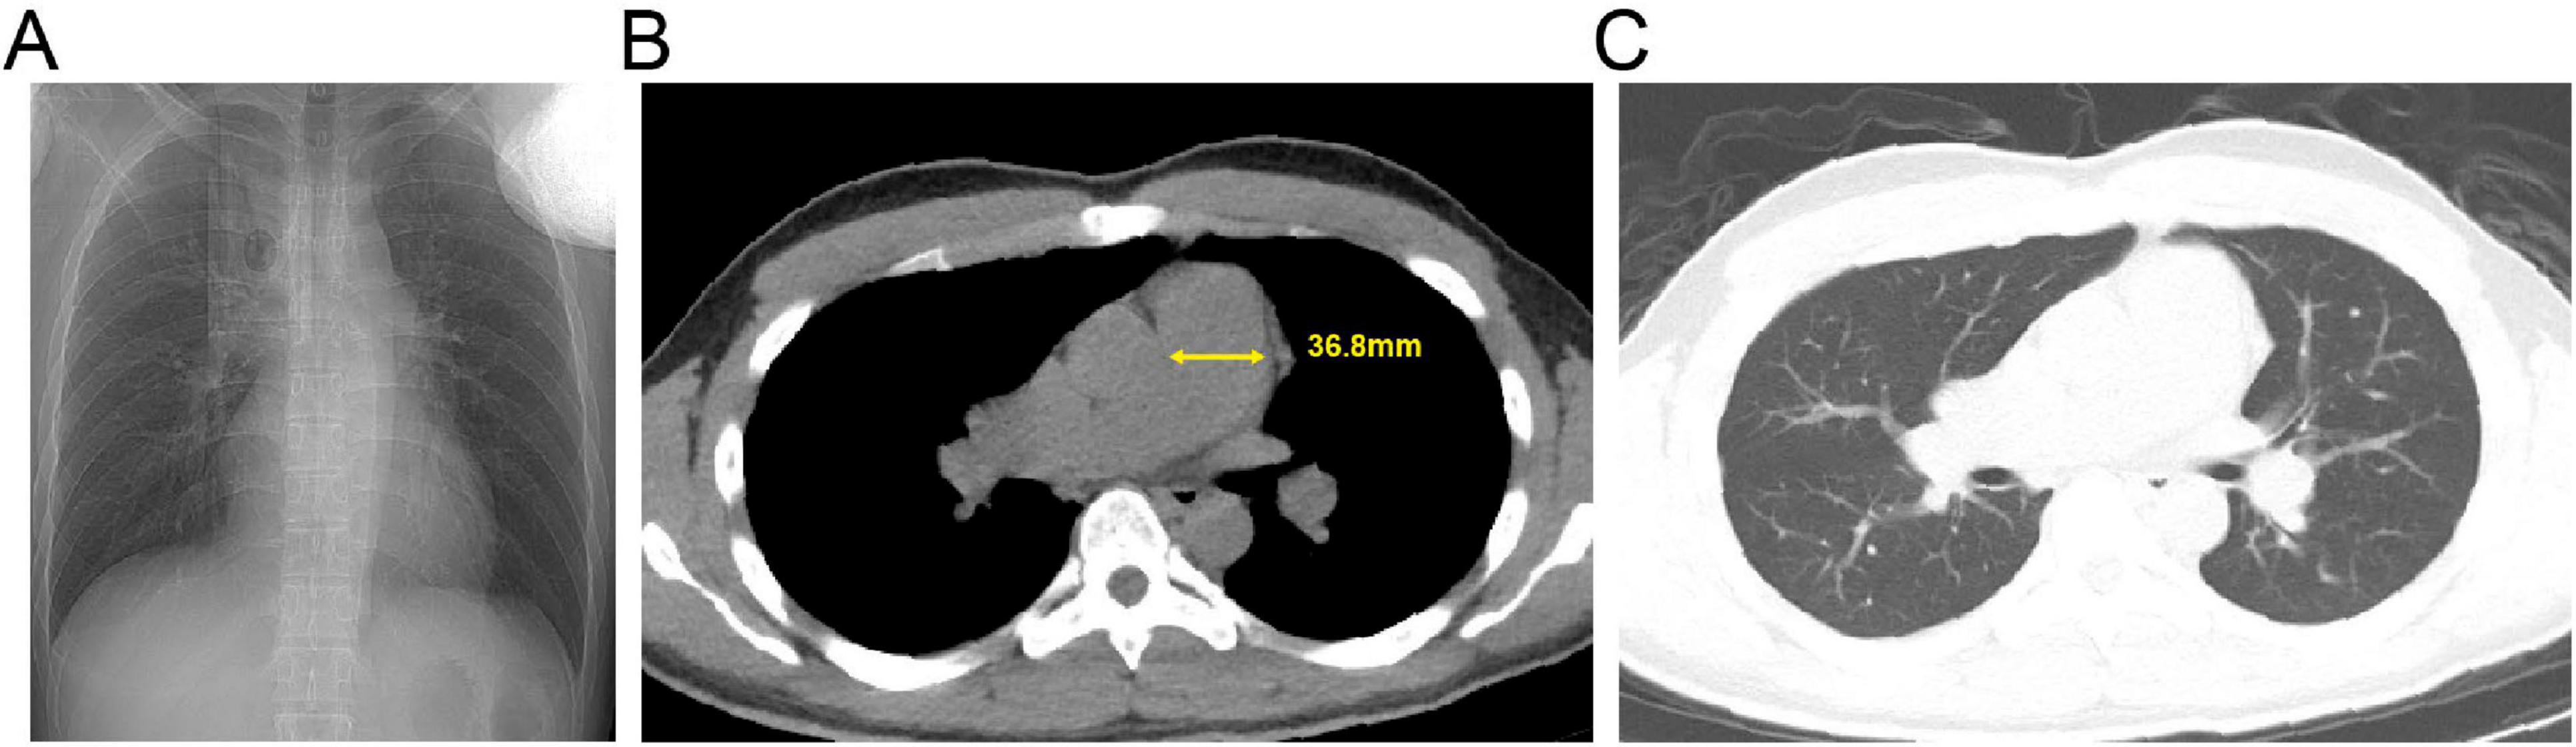

Background: The high-altitude environment characterized by hypobaric hypoxia can cause significant damage to the cardiovascular system, particularly vascular endothelial function, and is a significant trigger for acute and chronic mountain sickness. High-altitude pulmonary hypertension (HAPH) is a serious complication induced by prolonged exposure to high altitude, characterized by abnormally elevated pulmonary artery pressure and increased right heart load, which can progress to right heart failure and be life-threatening. This article aims to enhance clinicians' understanding of this disease through two cases of HAPH in young males. Case Description: Case 1 was a 21-year-old male who developed progressively worsening chest pain, shortness of breath, and amaurosis fugax after living at an altitude of 4800 meters for 4 months. Case 2 was a 20-year-old male who experienced exertional dyspnea accompanied by amaurosis fugax and a brief loss of consciousness after 18 months of residence at 4300 meters. Both patients were previously healthy with normal cardiopulmonary function before moving to high altitude. Physical examination upon presentation revealed significant hypoxemia (oxygen saturation 80% and 82% on room air, respectively). Echocardiography in both cases clearly demonstrated right atrial and right ventricular enlargement, moderate tricuspid regurgitation, with estimated systolic pulmonary artery pressures (sPAP) as high as 55 mmHg and 56 mmHg, respectively. Chest CT confirmed right heart enlargement and main pulmonary artery dilation. After systematic evaluation excluded other etiologies, HAPH was diagnosed. Discussion: The core pathophysiology of HAPH is hypoxia-induced pulmonary vasoconstriction and remodeling. These cases demonstrate that even for young, healthy individuals, prolonged exposure to extremely high altitudes can lead to severe pulmonary hypertension and right ventricular dysfunction. Diagnosis requires a combination of high-altitude exposure history, clinical symptoms, evidence of hypoxemia, and echocardiographic findings. The most fundamental treatment for diagnosed HAPH patients is removal from the high-altitude hypoxic environment, making early recognition and intervention crucial. Conclusion: The high-altitude environment poses a serious threat to the cardiovascular systems of susceptible individuals. For patients with a history of high-altitude residence who present with relevant symptoms, clinicians should maintain a high index of suspicion for HAPH and conduct timely screening and diagnosis to prevent adverse outcomes.